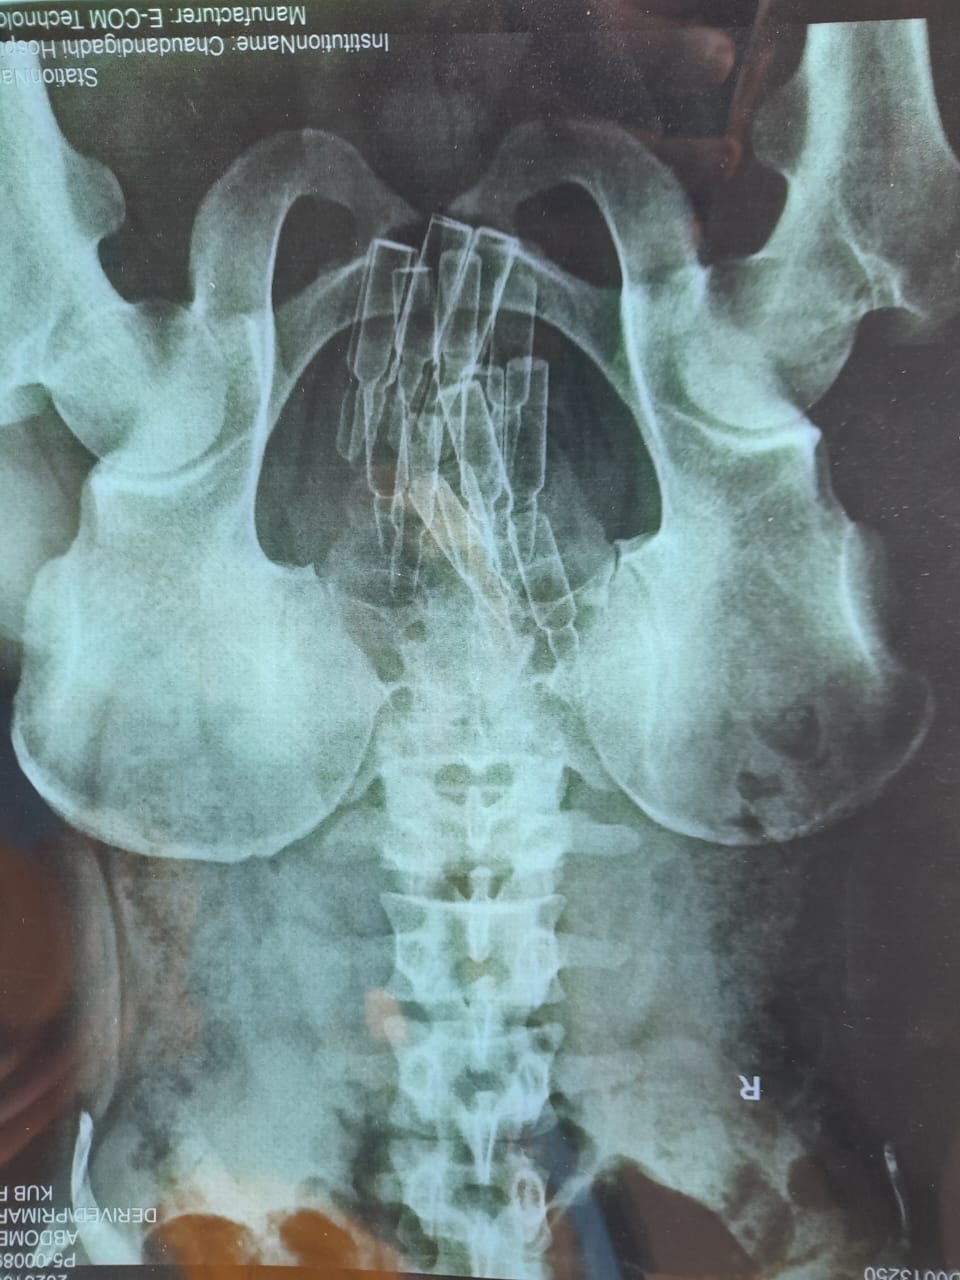

उनिहरुको साथ फेनारागन १४ एम्पुल,लुपिजेसिक ६ एम्पुल, डाईजेपाम ६, लेबल नभएको ९ एम्पुल गरी जम्मा ३५ एम्पुल लागुऔषाध प्रहरीले बरामद गरेको छ ।

बेल्टार प्रहरीका अनुसार लागुऔषाध सेवन गर्ने उदेश्यले शरिर भित्र (मलद्धारमा) गरी ल्याएको लागुऔषाध चौदण्डीगढी अस्पतालमा भिडियो एक्सरे गर्दा देखिएको थियो । सोही अनुसार तपशिलमा उल्लेखित लागू औषध निजहरुको शरिरबाट निकाली बरामद गरिएको प्रहरीको भनाई छ । उनिहरुलाई जिल्ला अदालतबाट दश दिनको म्याद थप गरी आवश्यक कानुनि कारवाहीको लागि अनुसन्धान भैरहेको छ ।